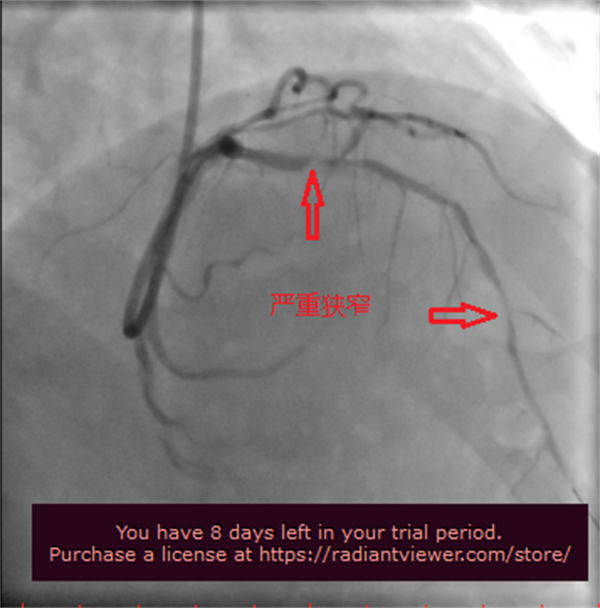

患者王先生,因“心绞痛”入住我院心内科,造影显示前降支严重钙化并重度狭窄,家人不愿意外科搭桥,希望能通过内科介入的方法治疗。北京阜外医院张海涛教授和我院心内科主任李钢、医生王志勇,根据患者的造影情况,充分考虑患者病情进行仔细研判,如果在术中直接进行球囊扩张,极有可能造成血管破裂、支架脱载等严重的并发症,甚至危及其生命,为确保手术成功,减少其并发症,经患者家属同意后,决定为王先生实施“冠状动脉旋磨术+支架植入术”。

考虑到患者病变钙化严重,为了精准评估病变和指导手术操作,最大程度保证安全性和效果,此次安排了光学相干断层成像(OCT)下辅助手术,还预备了各种术中可能用到的器械,如特殊指引导管、微导管、切割及棘突等多种球囊,并提前讨论了多套处理预案。